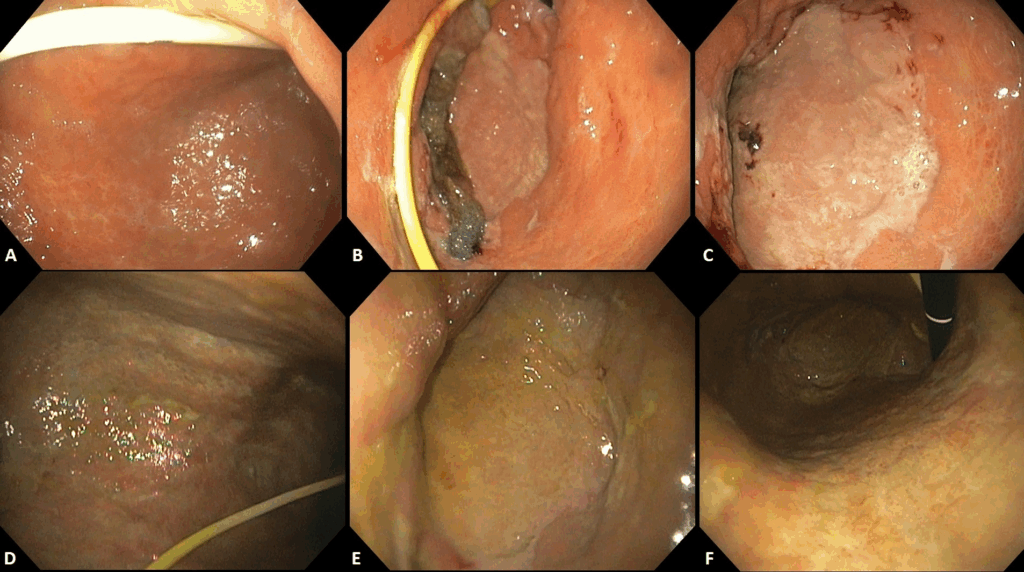

Figura 4 Adaptado de Dall’Agnol et al (9):

A-C: 21 dias de TEV

D-F: 1 semana após término da TEV